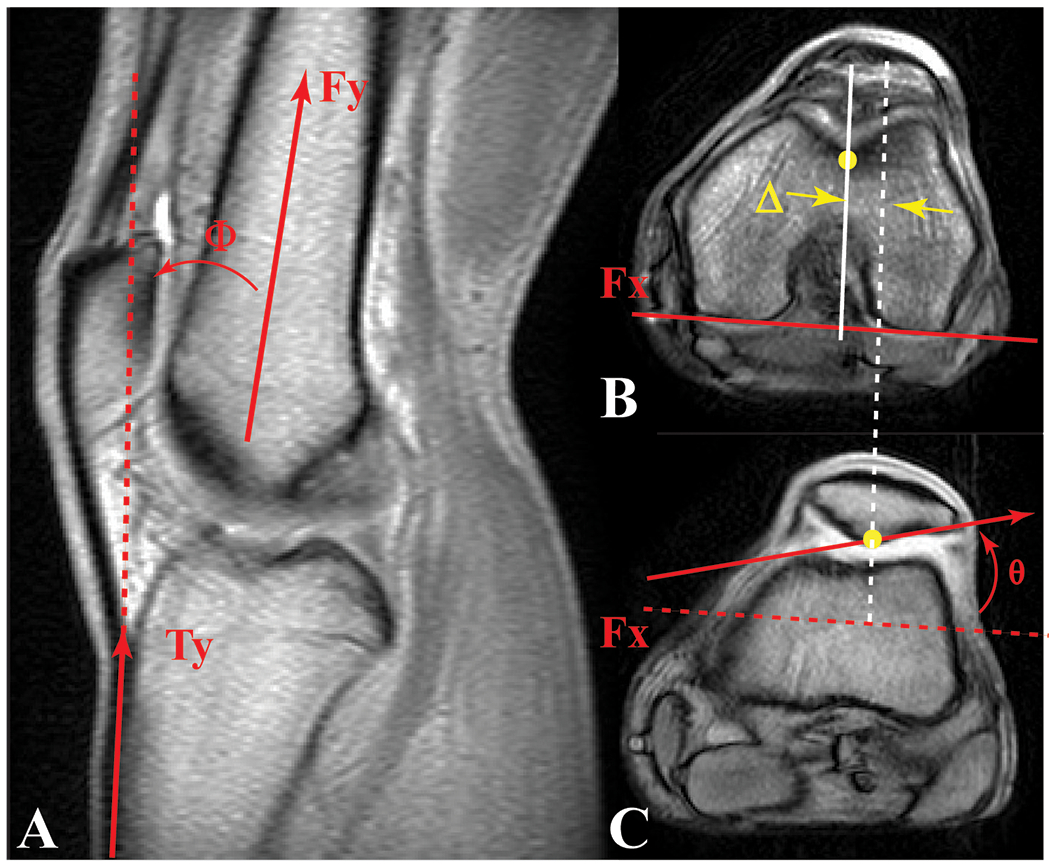

We measured patellar and tibial tracking relative to the femur using an anatomic coordinate system (Figure 1) constructed for each bone (Seisler and Sheehan, 2007). For the current study a knee angle of 10° is equivalent to full knee extension measured clinically using the hip, knee, and ankle centers of rotation (Freedman et al., 2014). Medial, superior, and anterior shift defined positive displacements. Three-dimensional mechanics convention (Mitiguy, 2011) established the rotation angles, with the order of positive rotation being flexion, medial tilt, and lateral spin (i.e., lateral spin is a varus rotation, which causes the superior pole of the patella to move laterally). We quantified the maltracking parameters for each participant in a PF pain cohort as the difference in each displacement and rotation variable relative to the mean from the age-matched control cohort. Thus, when visualizing maltracking graphically, the control mean is always zero. Axial plane tracking (Figure 1) consisted of medial-lateral shift and tilt of the patella relative to the femur.

Figure 1. Knee Angle, Lateral Patellar Shift, and Lateral Patellar Tilt.

A) Knee angle (Φ: the angle between a vector bisecting the distal femoral shaft and a vector parallel to the proximal anterior edge of the tibia) was measured in the full extension anatomical, sagittal, cine phase contrast image. A 10° knee angle measured on an MR image corresponded to a 0° clinical knee angle, measured using the hip, knee, and ankle (Freedman and Sheehan, 2013). Axial cine images for full extension at the B) level of the femoral epicondyle and C) mid-patellar level. Medial-lateral patellar shift (Δ) was defined as the distance from the patellar origin (most posterior patellar point on this image) to the femoral origin (deepest point in the sulcus at the level of the femoral epicondyle [B]), in the direction parallel to the posterior edge of the femur (Fx at the level of the femoral epicondyle [B]). Patellar tilt (θ) was defined as the angle between Fx and the lateral-posterior patellar edge. These three parameters (along with all patellofemoral superior, posterior displacement, flexion, and lateral spin) were then tracked throughout the motion cycle using the kinematic data derived from cine phase contrast MR imaging.